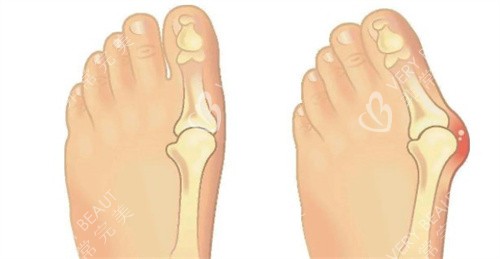

在追求美丽与健康的道路上,大脚骨问题成为了许多人的困扰。它不仅影响足部美观,还可能引发疼痛与功能障碍。北京广济医院凭借其在大脚骨治疗领域的卓然表现,成为了众多患者的信赖之选。下面,让我们深入了解一下这家医院。

医院重视患者的个体差异,针对不同病情和体质的患者,制定个性化的治疗方案。对于轻度外翻患者,可能建议采用支具调整结合改善训练;而中重度患者则需通过手术矫正骨骼和软组织平衡。这种个性化的治疗方案满足了患者的需求,确保了手术结果的满意度和自然度。

医生们在大脚骨手术方面积累了丰富的经验,掌握了优质的手术技巧。他们能够精细定位切口位置,减少手术创伤,提高手术成功几率。例如在手术中,能够同步处理关节和韧带平衡,从根上调整足弓结构,降低复发概率。